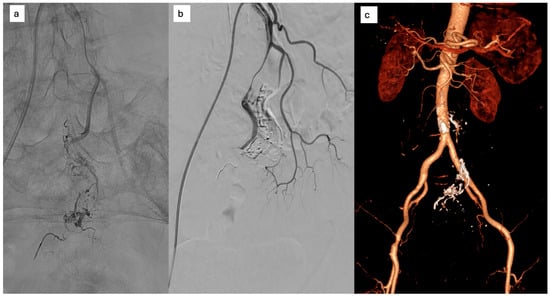

The patient was referred for multidisciplinary evaluation. Subsequent DSA confirmed a Yakes type IIa inferior mesenteric AVM, supplied by three arterial feeders originating from the IMA, with early venous filling and no evidence of portal hypertension. Given the patient’s symptoms and imaging findings suggestive of venous congestion, endovascular treatment was recommended. The procedure was performed via radial arterial access. After selective catheterization of the IMA, a microcatheter was advanced into one of the dominant feeding arteries. Embolization was achieved using a Glubran®–Lipiodol® mixture. Despite the presence of multiple arterial feeders, complete nidus exclusion was obtained after embolization through a single afferent vessel, with immediate cessation of early venous drainage (Figure 6).

Figure 6. (a) selective microcatheterization of the AMI and embolization with Glubran®–Lipiodol® mixture, (b) Complete nidus embolization after injection from a single feeding artery; (c) six-month CT: CT resolution of perivisceral congestion, without signs of recurrence.

The post-procedural course was uneventful. No antiplatelet or anticoagulant therapy was prescribed, as no arterial injury or flow-limiting dissection was observed. The patient reported rapid improvement of abdominal symptoms.